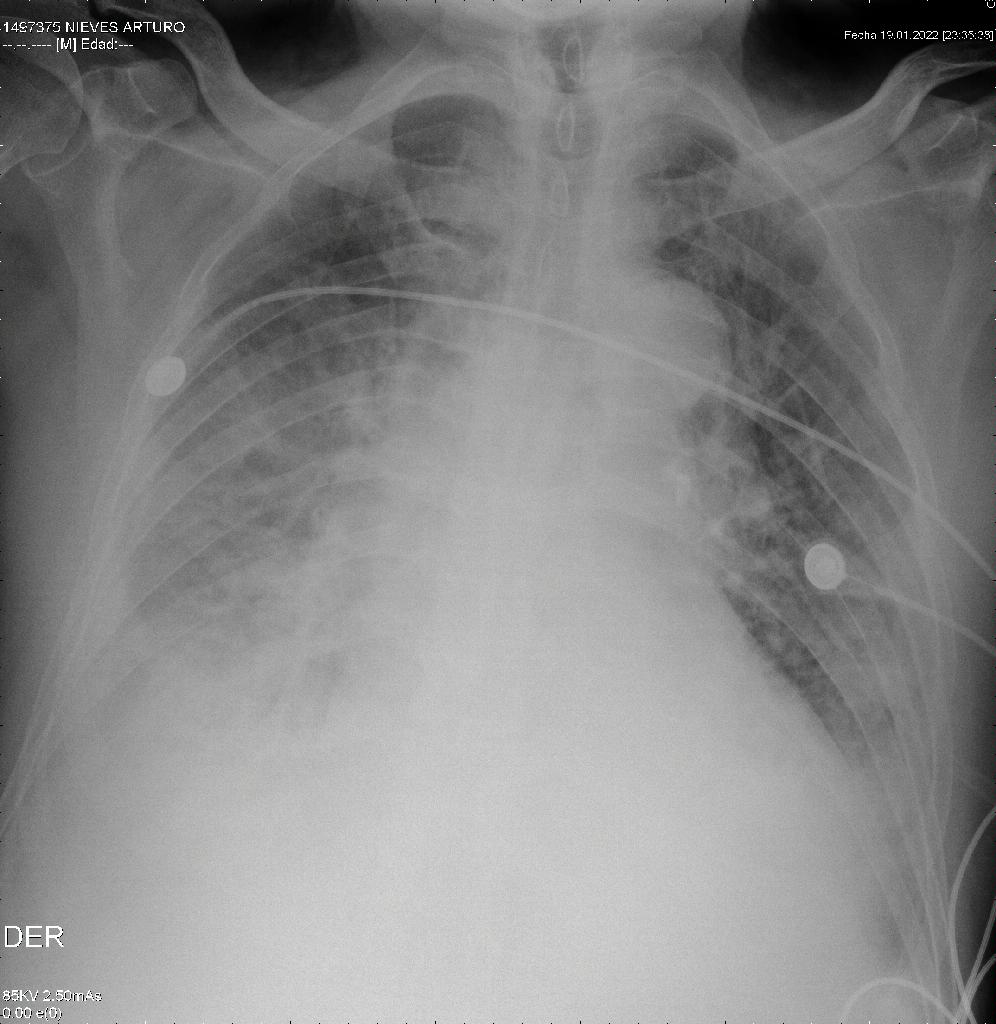

We present the case of an 83-year-old male patient with an incomplete COVID-19 immunization schedule and no influenza vaccination. His medical history included heart failure, severe aortic insufficiency, arterial hypertension, and a history of smoking. The patient was admitted to the emergency department on 01/13/23 with clinical symptoms of one month of evolution, including asthenia, adynamia, paroxysmal nocturnal dyspnea, orthopnea, and edema in the lower limbs. A diagnosis of decompensated congestive heart failure with acute pulmonary edema was established (Figure 1). A transthoracic echocardiogram performed on 01/21/2023 reported a left ventricular ejection fraction of 55%, a trivalve aortic valve with sclerosis and severe insufficiency, a 25 mm annulus, and mitral valve with moderate to severe insufficiency. Significant obstructive coronary artery disease was ruled out by cardiac catheterization on 01/26/2023. Subsequently, the patient was evaluated by the cardiac surgical board and was admitted to the protocol for transcatheter aortic valve implantation (TAVI).

Radiografía de tórax de ingreso 13/01/2023

Figure 1. Chest X-ray upon admission (01/13/2023)